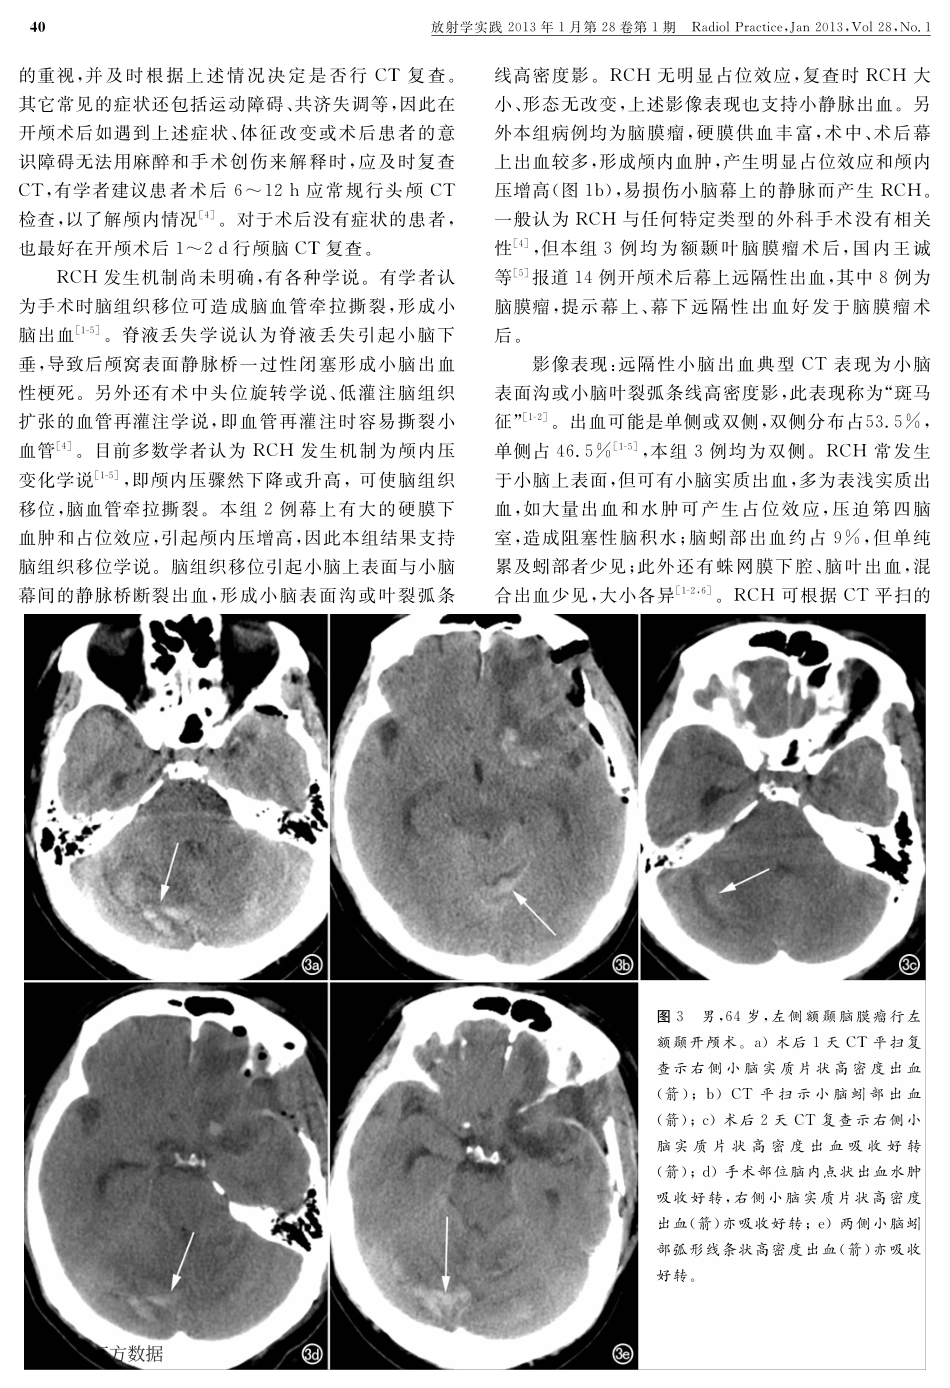

作者单位:437000湖北,咸宁市中心医院/华中科技大学同济咸宁医院影像科(章凯敏、杜希剑);430030武汉,华中科技大学同济医学院附属同济医院放射科(管汉雄、姜琼、周义成);430030武汉,华中科技大学同济医学院附属协和医院PET中心(贾清)作者简介:章凯敏(1978-),女,湖北咸宁人,主治医师,主要从事CT与MRI诊断工作。·中枢神经影像学·远隔性小脑出血CT表现章凯敏,杜希剑,管汉雄,贾清,姜琼,周义成【摘要】目的:探讨幕上开颅术后远隔性小脑出血(RCH)的临床及影像表现。方法:3例脑膜瘤患者行开颅手术后出现意识障碍,行紧急CT平扫发现并发RCH,回顾性分析RCH的临床及影像学表现。结果:2例术后手术部位可见大量硬膜下血肿及少量蛛网膜下腔�血,此2例可见两侧小脑上表面脑沟、脑叶�血,呈“斑马征”;1例手术后可见少量左侧小脑上表面叶及右侧天幕缘出血。结论:典型RCH表现为小脑单侧或双侧表面沟或小脑叶裂弧条线高密度影,呈“斑马征”,为其特征性CT表现,与术后颅内压突然增高或降低,引起脑组织移位,导致桥静脉断裂有关。【关键词】远隔性小脑出血;脑脊液;神经外科手术;体层摄影术,X线计算机【中图分类号】R651.1;R814.42【文献标识码】A【文章编号】10000313(2013)01003804犜犺犲犆犜犿犪狀犻犳犲狊狋犪狋犻狅狀狊犪狀犱犱犻犪犵狀狅狊犻狊狅犳狉犲犿狅狋犲犮犲狉犲犫犲犾犾犪狉犺犲犿狅狉狉犺犪犵犲ZHANGKaimin,DUXijian,GUANHanxiong,etal.DepartmentofMedicalImaging,XianningCentralHospital,Hubei437000,P.R.China【犃犫狊狋狉犪犮狋】犗犫犼犲犮狋犻狏犲:Toinvestigatetheclinicalandimagingmanifestationsofremotecerebellarhemorrhage(RCH)aftersupratentorialcraniotomies.犕犲狋犺狅犱狊:Threepatientsofmeningiomahadunconsciousnessoccurredaftersupratentorialcraniotomy,RCHwasfoundonCTwithoutcontrastenhancementduringemergency.TheclinicalandimagingmanifestationsofRCHwereretrospectivelyanalyzed.犚犲狊狌犾狋狊:Massivesubduralhematomaandasmallamountofsubarachnoidhemorrhagelocatedattheoperationregionwerefoundintwopatients,withbilateralsuperficialcerebellarsulciandlobarhemorrhage,showingas“ZebraSign”.Thethirdpatientpresentedwithsmallamountofhemorrhageintheleftsuperiorsulciandrightinfratentorialregion.犆狅狀犮犾狌狊犻狅狀:ThetypicalCTmanifestationsofRCHappearsashighdensityinunilateralorbilateralsuperficialsulciorcerebellarfissures,whichisreferredas“ZebraSign”.ItisbelievedthatRCHisrelatedtosuddenincreaseordecreaseofintracranialpressure,displacementofbraintissue,whichleadstolacerati...